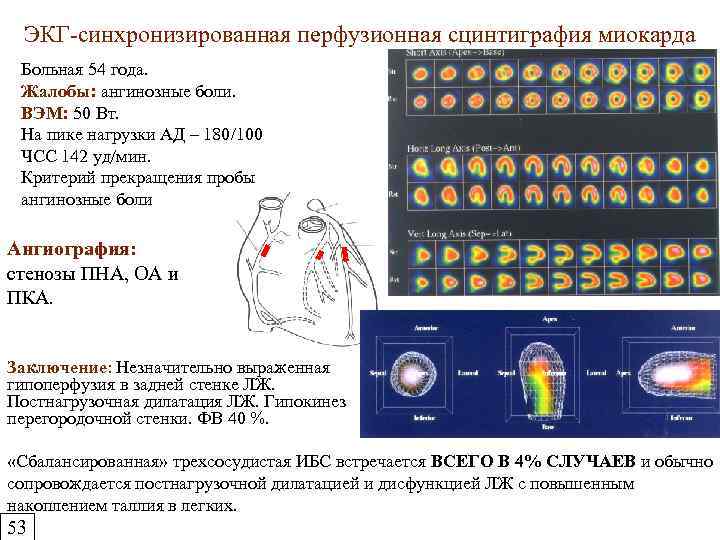

ЭКГ-синхронизированная перфузионная сцинтиграфия миокарда Больная 54 года. Жалобы: ангинозные боли. ВЭМ: 50 Вт. На пике нагрузки АД – 180/100 ЧСС 142 уд/мин. Критерий прекращения пробы ангинозные боли Ангиография: стенозы ПНА, ОА и ПКА. Заключение: Незначительно выраженная гипоперфузия в задней стенке ЛЖ. Постнагрузочная дилатация ЛЖ. Гипокинез перегородочной стенки. ФВ 40 %. «Сбалансированная» трехсосудистая ИБС встречается ВСЕГО В 4% СЛУЧАЕВ и обычно сопровождается постнагрузочной дилатацией и дисфункцией ЛЖ с повышенным накоплением таллия в легких. 53

ЭКГ-синхронизированная перфузионная сцинтиграфия миокарда Больная 54 года. Жалобы: ангинозные боли. ВЭМ: 50 Вт. На пике нагрузки АД – 180/100 ЧСС 142 уд/мин. Критерий прекращения пробы ангинозные боли Ангиография: стенозы ПНА, ОА и ПКА. Заключение: Незначительно выраженная гипоперфузия в задней стенке ЛЖ. Постнагрузочная дилатация ЛЖ. Гипокинез перегородочной стенки. ФВ 40 %. «Сбалансированная» трехсосудистая ИБС встречается ВСЕГО В 4% СЛУЧАЕВ и обычно сопровождается постнагрузочной дилатацией и дисфункцией ЛЖ с повышенным накоплением таллия в легких. 53